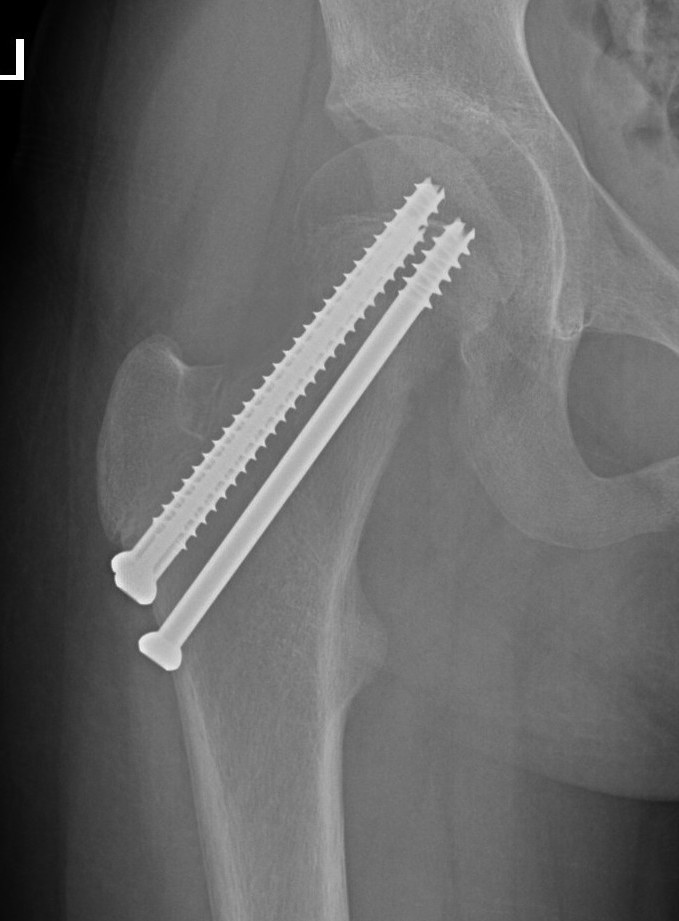

Fixation

- < 3 years K wires crossing physis

- > 3 cannulated screws crossing physis

Spica post op < 10 years

- < 3 years K wires

- > 3 cannulated screws / pediatic hip screw